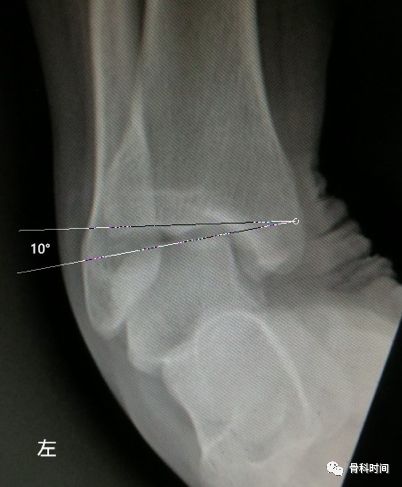

28 岁青年女性,约 2 年前左踝首次发生崴脚,未行外固定处理,近 1 年来左踝间断多次崴脚,双侧踝关节应力正位片测量距骨倾斜角,左侧为 10°,右侧 4°,左侧应力位状态下感疼痛,右侧无不适感,考虑左侧踝关节不稳。